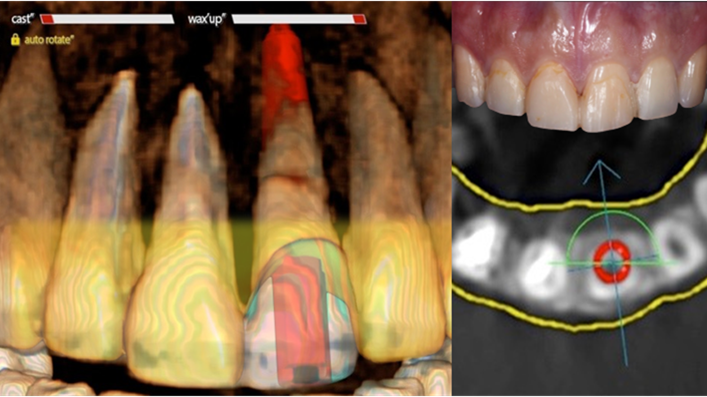

Clinical case: Extraction, immediate placement & loading using

R2GATE solution in aesthetic zone

- Courtesy of Dr. Jong-Cheol Kim, Korea-